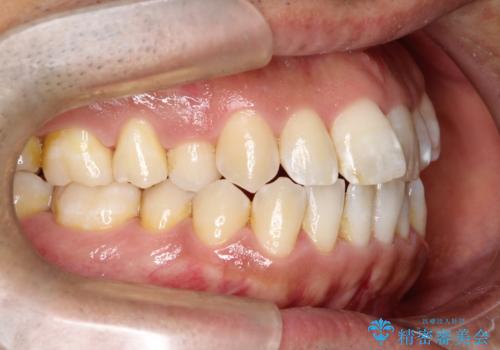

- 左上の八重歯を気にされて来院されました。精密な検査の結果、歯列全体を広げながら八重歯を奥へ移動させることで、美しい歯並びと機能的な咬み合わせが得られると診断。患者様のご希望に合わせ、透明で目立ちにくい**インビザライン(マウスピース矯正)**による治療計画を立案しました。抜歯を避け、歯を少しずつ遠心(奥)へ移動させることで、歯が並ぶスペースを確保し、叢生(歯のデコボコ)を改善します。

今回の矯正治療では、透明なマウスピース型の装置インビザラインを使用しました。この装置は目立ちにくく、取り外しが可能なため、食事や歯磨きも普段通りに行えます。遠心移動という方法で奥歯を後方に動かし、前歯を並べるためのスペースを確保。これにより、抜歯することなく、左上の八重歯を含む叢生を効果的に改善し、整った美しい歯並びと良好な咬み合わせを獲得していただけました。